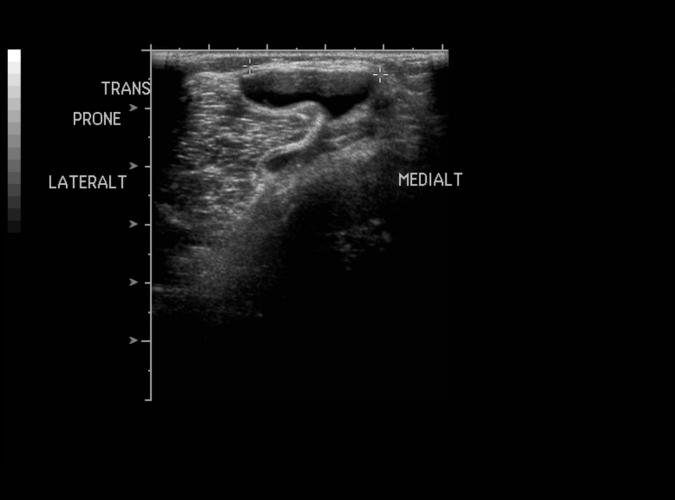

Patologi.

Bakercysta.